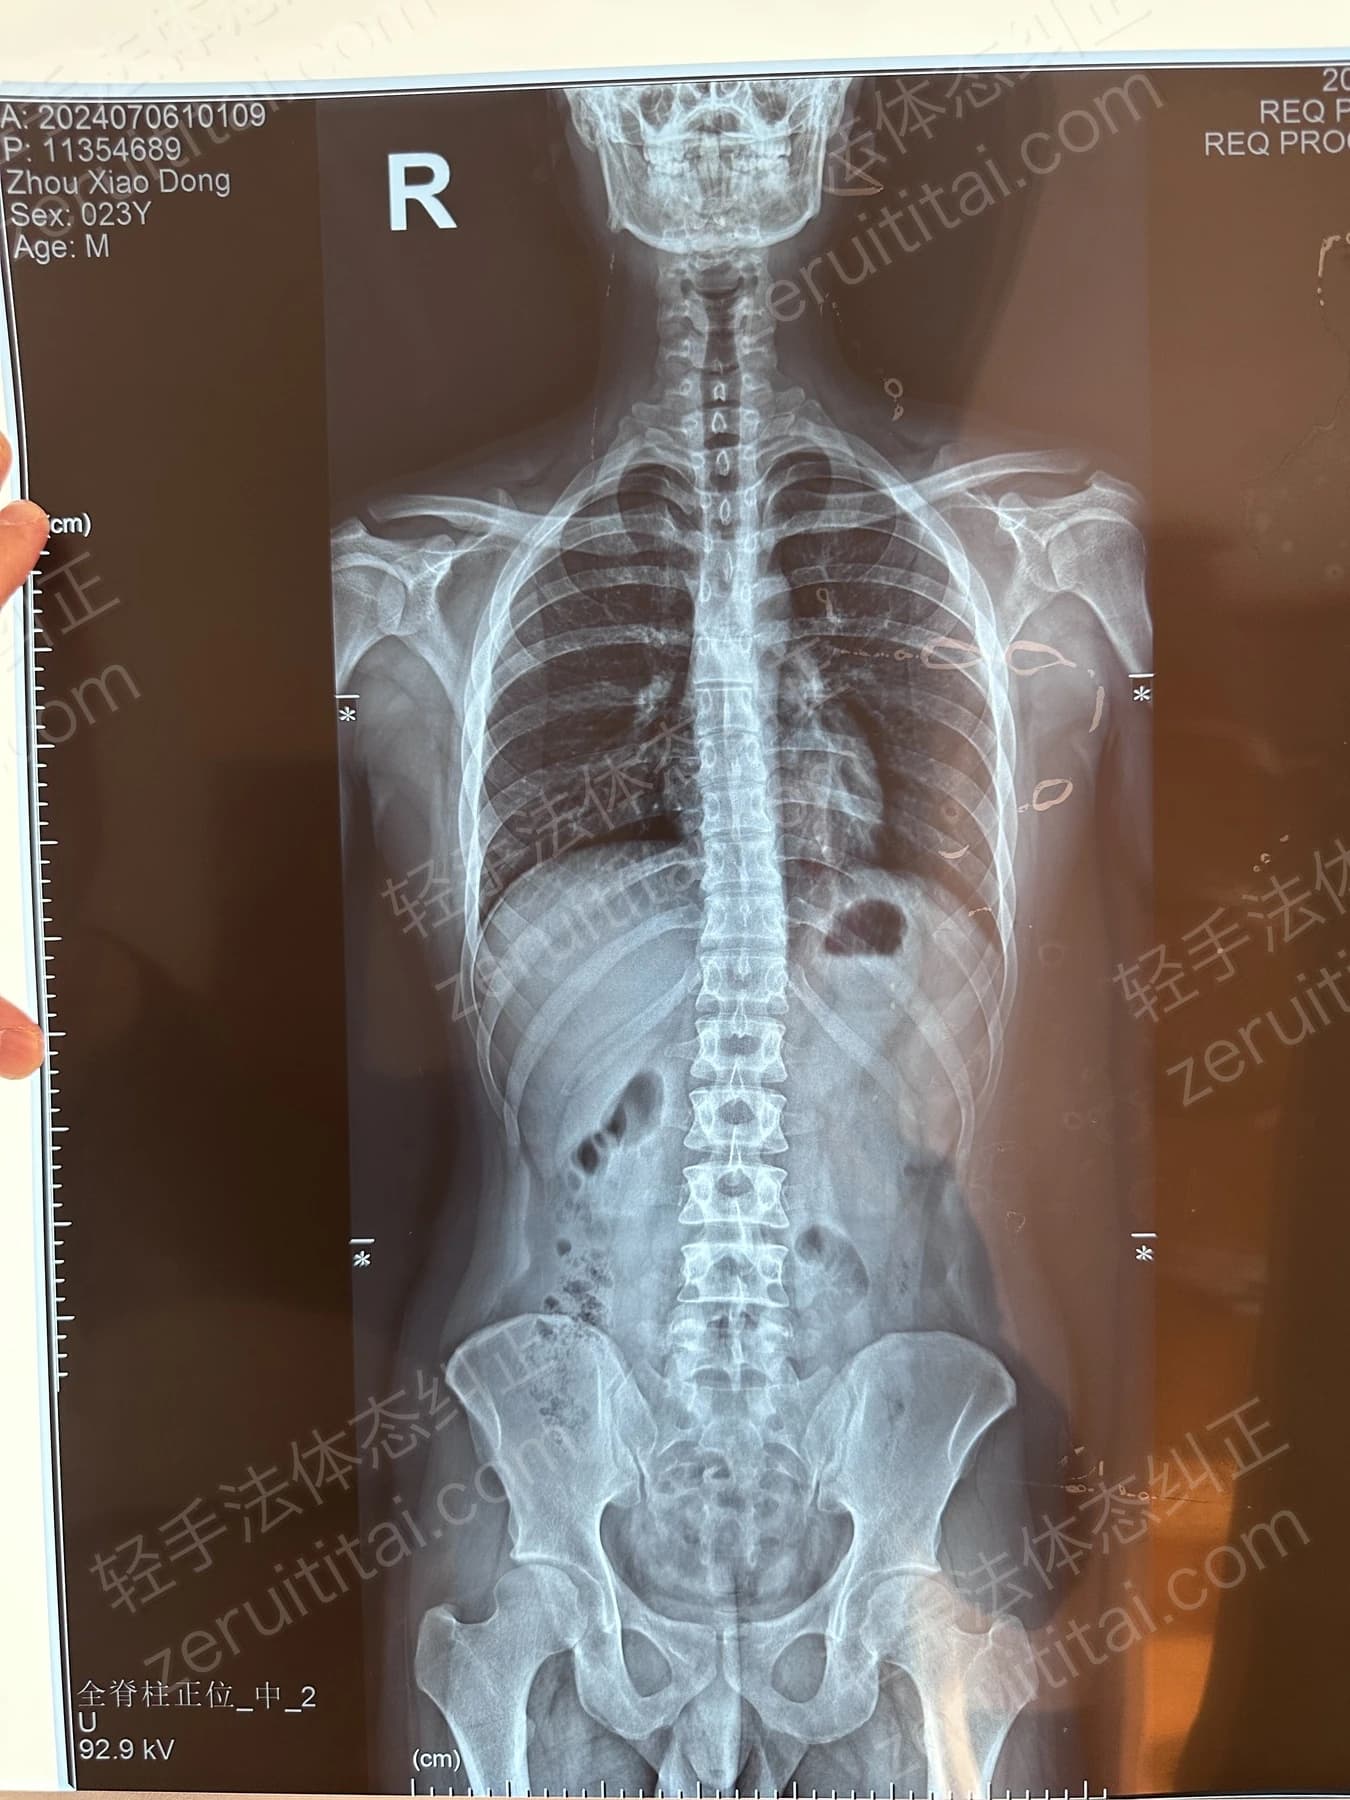

2022.06.27

第 1 次记录